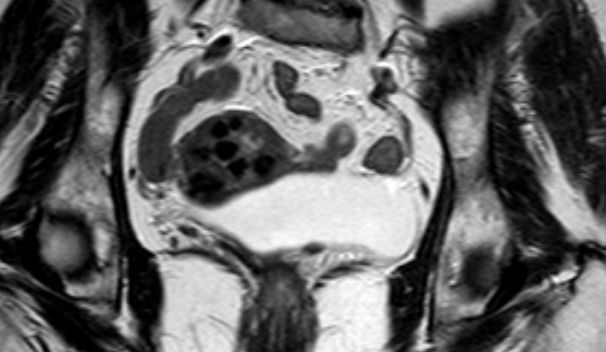

MRT T2W TSE. 61-jährige Frau mit Uterus myomatosus.